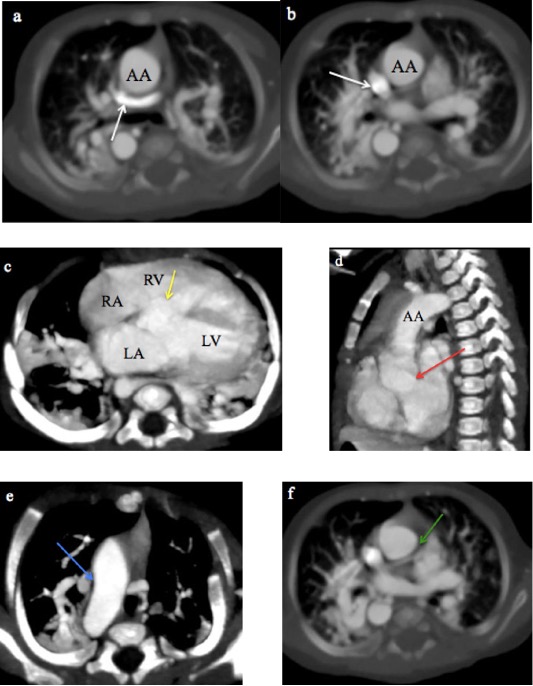

MDCT images of TAPVC are shown in Figures 4 and 5, demonstrating the characteristic drainage patterns of the supracardiac and infracardiac types, respectively.

Fig. 4 A 2-month male infant with supracardiac total anomalous pulmonary venous connection. (a-b) CT Pulmonary angiography axial MIP sequential images from caudal to cranial levels showing the left pulmonary veins (LPV) and right pulmonary veins (RPV) converging to form a vertical vein (VV) that drains into the superior vena cava (SVC). (c-d) Coronal MIP images demonstrating the VV draining into the SVC.

Fig. 5 A month old male infant with infracardiac total anomalous pulmonary venous connection. a) CT Pulmonary angiography coronal MIP and b) 3-D volume-rendered CT images show the right and left superior and inferior pulmonary veins (RCPV and LCPV) joining to form a vertical vein (white arrow) that descends through the diaphragm and drains into a dilated and tortuous splenic vein (SV).

TAPVC, in which all four pulmonary veins drain into the systemic veins rather than the left atrium, is usually diagnosed on echocardiography4. However, MDCT angiography is indispensable when echocardiographic visualization is limited or complex CHD is suspected. The supracardiac type of TAPVC was the most common in this study (45.5%), consistent with previous reports (45%-55%)8,10. In our study, MDCT angiography effectively characterised various drainage patterns, including a supracardiac TAPVC draining into the SVC and a rare infracardiac type of TAPVC draining into the splenic vein, also reported by AI Mutari et al26. MDCT’s 3D reconstructions provided crucial details for accurate delineation of venous stenosis.